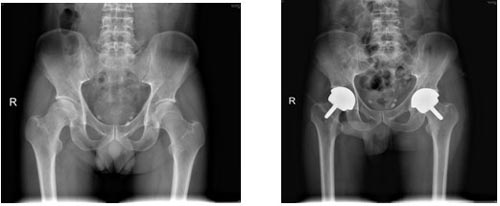

典型病例:男性43岁,因双侧股骨头坏死行双侧表面髋关节置换